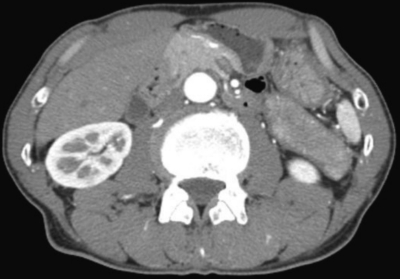

血液所見:赤血球 423 万、Hb 12.9 g/dL、Ht 37 %、白血球 6,400、血小板 21 万。血液生化学所見:尿素窒素 13 mg/dL、クレアチニン 0.5 mg/dL、総蛋白 8.5 g/dL、アルブミン 3.9 g/dL、IgG 3,305 mg/dL (基準 960〜1,960)、IgA 159 mg/dL (基準 110〜410)、IgM 67 mg/dL (基準 65〜350)、IgE 350 IU/mL (基準 250 以下)、総ビリルビン 0.9 mg/dL、AST 22 U/L、ALT 16 U/L、γ-GTP 34 U/L (基準 8〜50)、アミラーゼ 122 U/L (基準 37〜160)。免疫血清学所見:抗核抗体陰性、リウマトイド因子<RF>陰性。眼窩部単純CT及び腹部造影CTを別に示す。